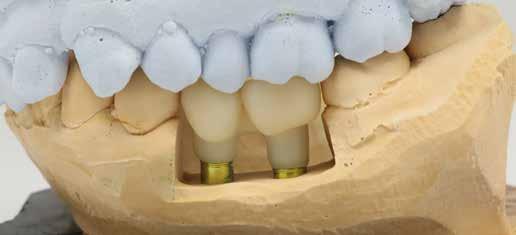

A 75 éves páciens új fogsorokat szeretett volna. Felül nem kielégítő teljes lemezes kivehető fogsora volt, alul pedig szintén nem megfelelő részleges fogsora, néhány devitális, apikális oszteolízist és masszív szekunderkárieszt felmutató mutató maradék frontfogon. Az endodonciai beavatkozást a páciens elutasította. Ehelyett kerámiaimplantátumokra alapozott kezelést kívánt. Az úr általános egészségi állapotában panaszok mutatkoztak. A CMD-index nem volt számottevő. A DVT-vizsgálat (1. kép) alapján megállapítható a 42-es fog decens apikális oszteolízise, számottevő vertikális és horizontális csontveszteség a rágóterületen, valamint az

1. kép: Kiindulási helyzet: az OPG hat devitalizált alsó frontfogat ábrázol, részleges apikális oszteolízissel, szekunderkáriesszel, horizontális csontfelszívódással a rágóterületen.

2. kép: 6 egyrészes SDS kerámiaimplantátum azonnal behelyezve az extrakciót követően.

3. kép: A laborkészítésű formát felhasználva alakították ki az ideiglenest.

4. kép: Kontrollfelvétel: a posztoperatív helyzet az ideiglenessel a hat implantátumon.

FDOK/NICO értelmében HU alapján mért erőteljes csontsűrűség-csökkenés mutatkozik az 18, 17, 13, 23, 27 és 28 fogak régiójában.

Terápia és implantáció

Az operatív beavatkozás előtt a behelyezett fogsorokkal és azok nélkül is beszkennelték az intraorális szituációt, valamint elkészítették a fogsorok digitális másolatát. Ezután óvatosan kihúzták a maradék fogakat, és mindent előkészítettek az azonnali implantációhoz, amelynek során 6 egyrészes SDS kerámiaimplantátumot terveztek behelyezni a meglévő alveolusba a 34-43 közötti területre. Közvetlenül a behelyezést megelőzően a szék mellett még egyszer megtisztították Diener Denta Plas plazmakészülékkel (lásd 49. kép) az implantátumokat, a lehető legteljesebb csírátlanítás – így a páciens csíraterhelésének minimalizálása – érdekében (2. kép) Az alveolus ózonos tisztítását követően behelyezték a hat egyrészes SDS kerámia-implantátumot, A-PRF (saját vérlemezkében gazdag – a ford.) membránokkal megsegítve. A laborkészítésű előre mintázott elemek alapján azonnali ide-

iglenes került az implantátumokra (3. kép), majd röntgennel újólag ellenőrizték a létrejött helyzetet (4. kép)

5–6. képek: A gyógyulási fázist követően az egyrészes implantátumokat csonkszerűvé alakították.

7–12. képek: A digitális lenyomatvétel. A harapást a régi fogsorokra alapozták, a digitális lenyomat arcbeolvasás után, virtuálisan készült. Miután a páciens így gyakorlatilag heti hét napon át 24 órát is „ülhetett” a laborban, időfüggetlen arcanalízist készíthettünk, a fogakat pedig annak alapján állíthattuk fel. A két alsó stéget „visszafelé” tervezéssel valósítottuk meg.